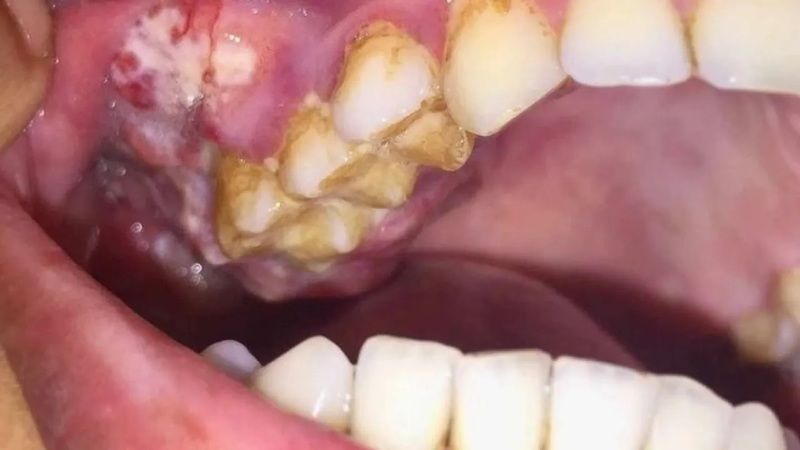

AĞIZ KANSERİ NEDİR?

Ağız kanseri alt dudak başta olmak üzere, gırtlak, bademcikler, ağız içi ya da tükürük bezlerinin arkasında bulunan bölgeleri kapsayan kanser türü olarak tanımlanmaktadır. Erken teşhis ile önlenebilen bu kanser türü, az bilinen birçok belirtiye sahiptir.